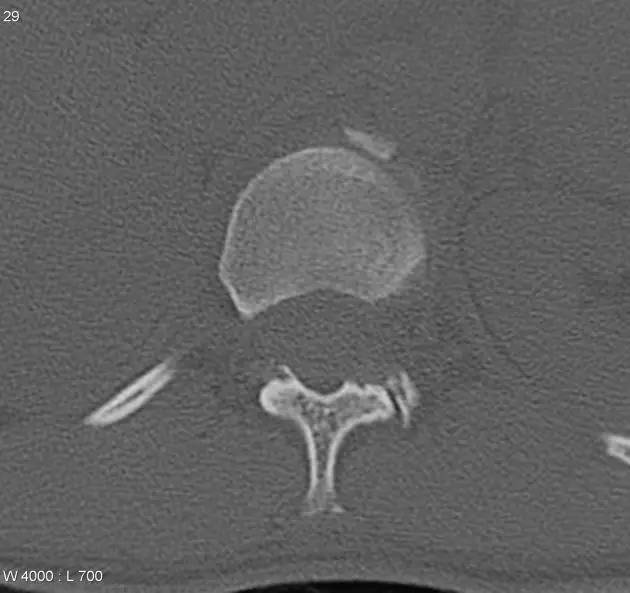

5. Hoffa 骨折

指股骨远端冠状面的骨折。

病例 1:一般股骨髁间、髁上粉碎骨折中含 Hoffa 骨折的不少见,但单纯后髁骨折则很少见。

正位片

侧位片

水平位 CT

第 2 例

第 3 例